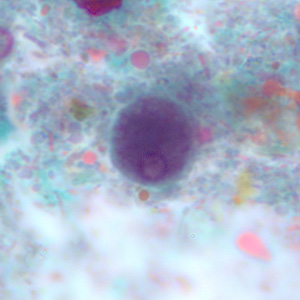

E.histolytica cyst

four nuclei and a chromatoid body with blunt ends